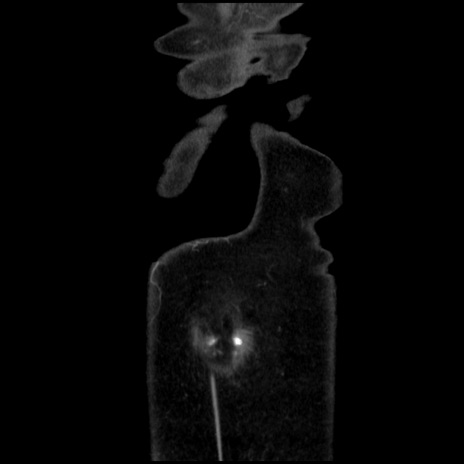

矢状断像

【症例】40歳代 女性

【主訴】上腹部痛、嘔気・嘔吐

【現病歴】約9時間前頃から急に上腹部痛、嘔気、嘔吐が出現。改善しないため救急要請。

【既往歴】子宮頚癌(広汎子宮全摘術、放射線療法)、腸閉塞